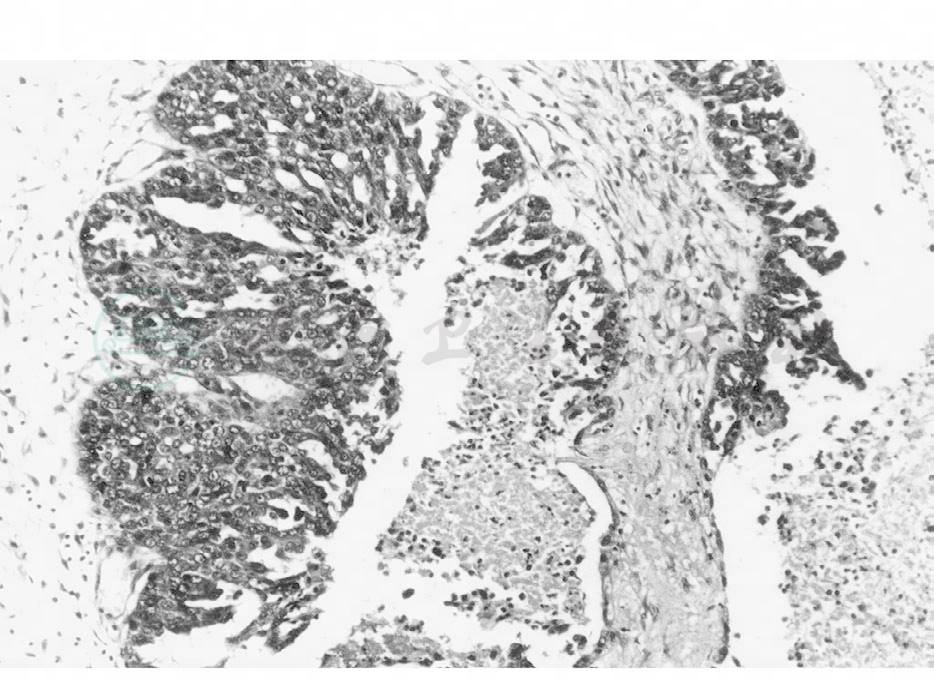

包括浆液性腺癌、浆液性乳头状腺癌及浆液性乳头状囊腺癌。浆液性腺癌为米勒管型上皮的恶性肿瘤,其癌细胞常以形成囊腔和乳头为特征,但或多或少仍保留原来的组织形态。有的肿瘤形成大且不规则的小囊腔,有时上皮突入腔内形成上皮簇或乳头的倾向(图1)。

图1 卵巢浆液性乳头状囊腺癌